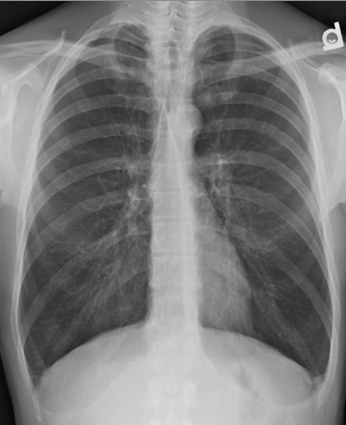

What features on this CXR are indicative of COPD?

Flattened hemi-diaphragms

Narrow mediastinum

Hyperinfalted lungs

Barrel chest